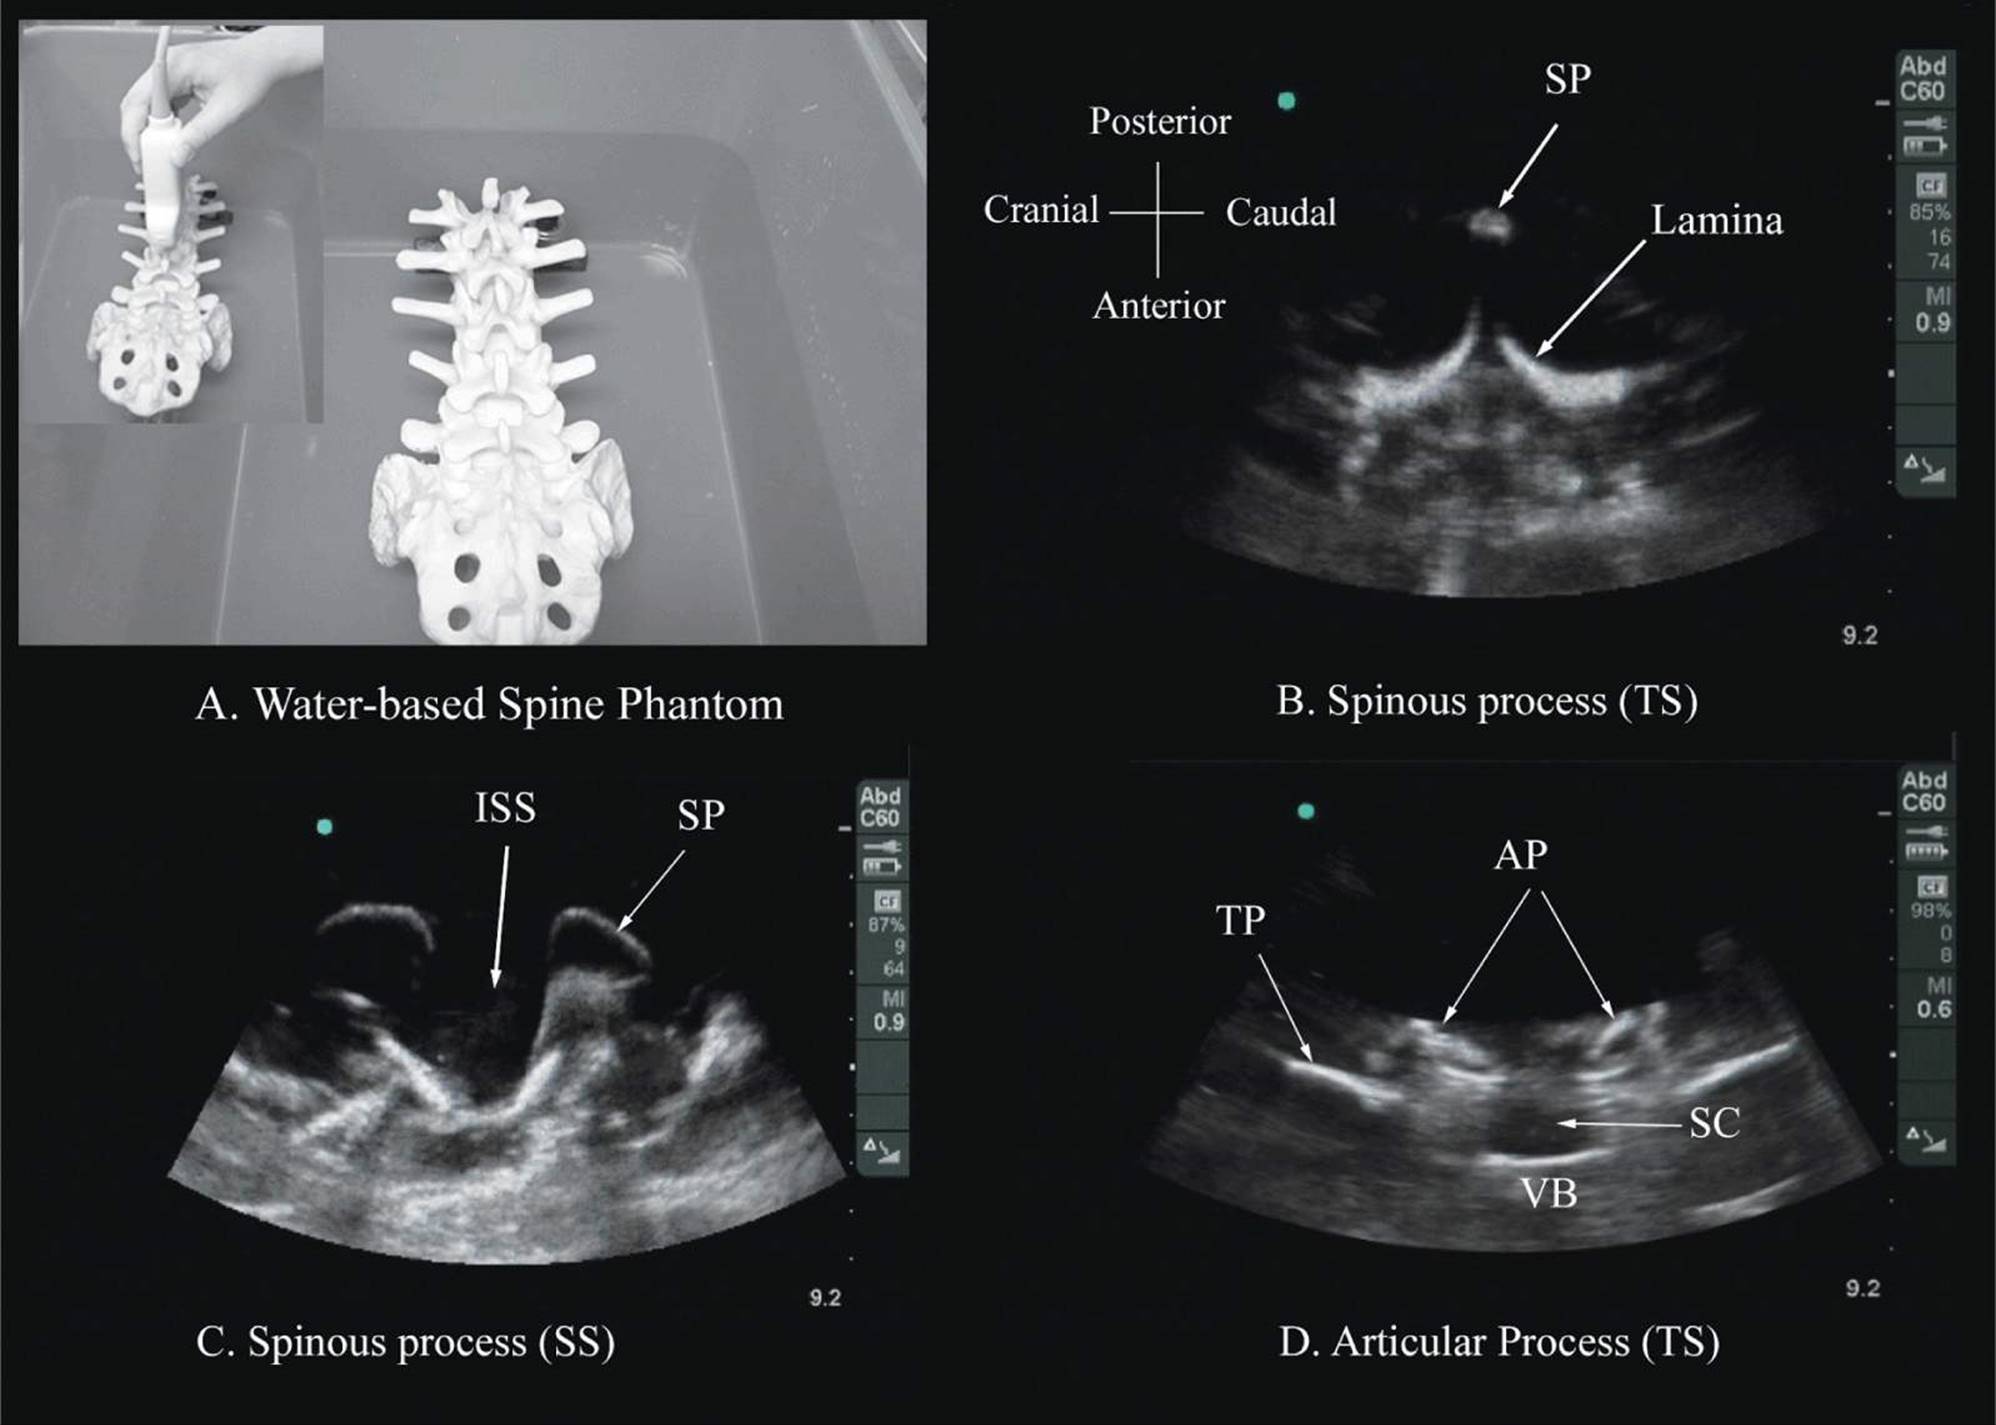

Several anatomic models recently became available that can be used to learn musculoskeletal US imaging techniques (human volunteers), the sonoanatomy relevant for peripheral nerve blocks (human volunteers or cadavers), and the required interventional skills (tissue mimicking phantoms, fresh cadavers). However, few models or tools are available to learn and practice spinal sonoanatomy or the interventional skills required for US-guided CNB. Karmakar and colleagues recently described the use of a “water-based spine phantom” (Figure 44-3A) to study the osseous anatomy of the lumbosacral spine16,18 and a “pig carcass phantom” model19 (Figure 44-4A) to practice the hand-eye coordination skills required to perform US-guided CNB.19 Computer-generated anatomic reconstruction from the Visible Human Project data set that corresponds to the US scan planes is another useful way of studying the sonoanatomy of the spine. Multiplanar three-dimensional (3D) reconstruction from a high-resolution 3D computed tomography (CT) data set of the spine can be used to study and validate the sonographic appearance of the various osseous elements of the spine (Figure 44-5).

FIGURE 44-3. (A) The water-based spine phantom and sonograms of the spinous process in the (B) transverse and (C) midsagittal or median axes, and (D) a scan through the interspinous space. SP, spinous process; ISS, interspinous space; TP, transverse process; AP, articular process; SC, spinal canal; VB, vertebral body; TS, transverse scan; SS, sagittal scan.

Water-Based Spine Phantom

The water-based spine phantom18 is based on a model described previously by Greher and colleagues to study the osseous anatomy of relevance to US-guided lumbar facet nerve block.20 The model is prepared by immersing a commercially available lumbosacral spine model in a water bath. A low-frequency curved array transducer submerged into water is used to scan in the transverse and sagittal axes (Figure 44-3A). Each osseous element of the spine produces a “characteristic” sonographic pattern. The ability to recognize these sonographic patterns is an important step toward understanding the sonoanatomy of the spine. Representative US images of the spinous process, lamina, articular processes, and the transverse process from the water-based spine phantom are presented in Figures 44-3 and 44-6. The advantage of this water-based spine phantom is that water produces an anechoic (black) background against which the hyperechoic reflections from the bone are clearly visualized. The water-based spine phantom allows a see-through real-time visual validation of the sonographic appearance of a given osseous element by performing the scan with a marker (e.g., a needle) in contact with it (Figure 44-6A). The described model is also inexpensive, easily prepared, requires little time to set up, and can be used repeatedly without deteriorating or decomposing, as animal tissue-based phantoms do.